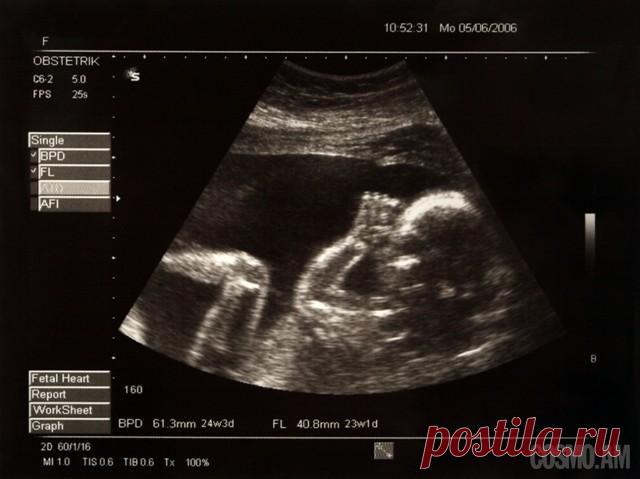

Аплодисменты в животике у мамы